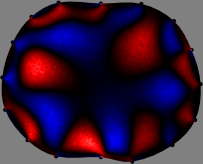

Figs. 3 and 4 compare the performance of the proposed FER method in (20) with the standard regularized least-squares method ((19) when \mathcal{R} is the identity matrix). The regularization parameter of the standard method was heuristically chosen for its best performance, and the parameter of the FER method was set to be one of three different values λ=0.05,0.2,𝜆0.050.2\lambda=0.05,0.2,\infty. The injection current was 1 mARMSRMS{}_{\tiny{\mbox{RMS}}} at 100 kHz, and the frame rate was 9 frames per second. The reference frame at t0subscript𝑡0t_{0} was obtained from the maximum expiration state. The measured data, 𝐕˙(tm)˙𝐕subscript𝑡𝑚\dot{\mathbf{V}}(t_{m}), represent the voltage differences between each time tmsubscript𝑡𝑚t_{m} and t0subscript𝑡0t_{0}. The blue regions, which denote where conductivity decreased by inhaled air, increased during inspiration and decreased during expiration. The FER method with λ=𝜆\lambda=\infty was clearly more robust than the standard method that produced more artifacts originated from the inversion process.

Figure 4: The reconstructed images of the conductivity change of the subject B by the standard regularized least square method and the proposed fidelity-embedded regularization (FER) method for three difference values λ=0.05,0.2,𝜆0.050.2\lambda=0.05,0.2,\infty. Here, the time step is 0.55 seconds (tm+5tm0.55subscript𝑡𝑚5subscript𝑡𝑚0.55t_{m+5}-t_{m}\approx 0.55).